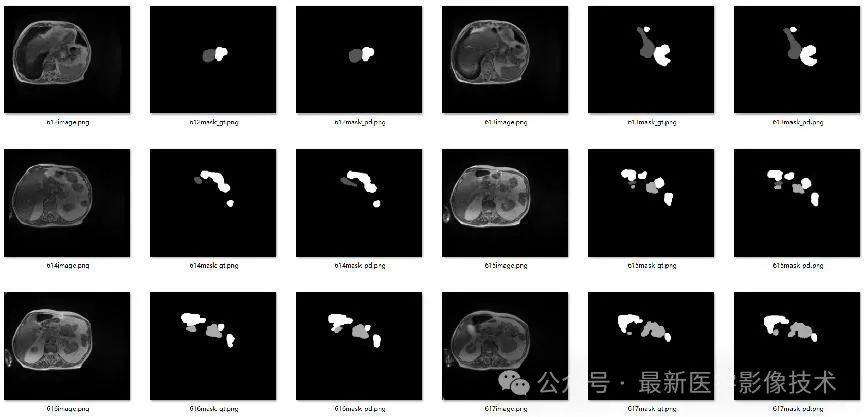

4、验证集部分分割结果